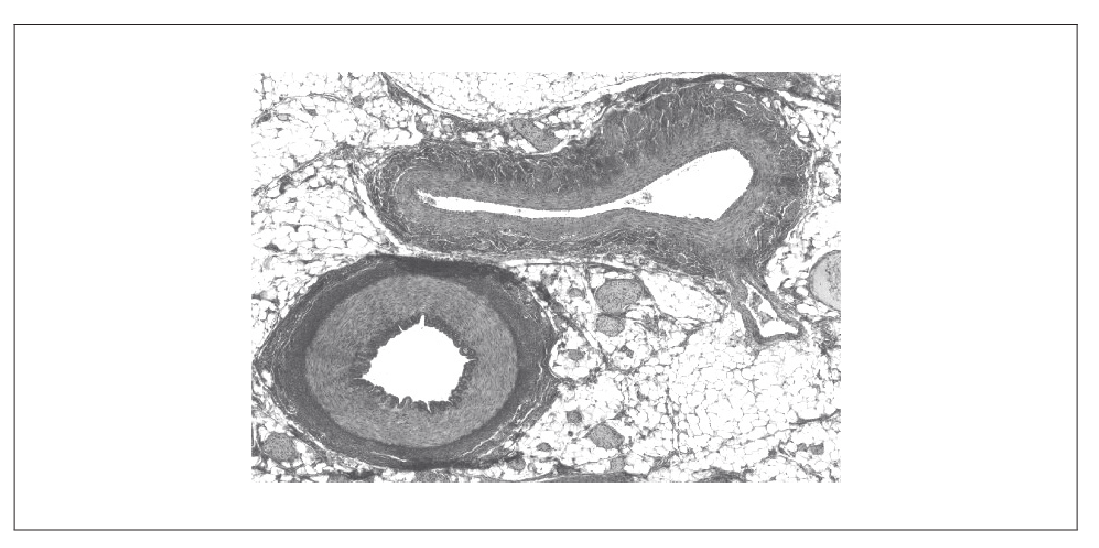

The micrograph shows a transverse section through blood vessels of a mammal.

Identify the vein by labelling it with the letter V.

Distinguish between the vein and the artery with reference to structures visible in the micrograph.

label pointing to the upper of the two blood vessels in the micrograph

a. vein has larger lumen

b. vein has less elastic tissue

c. vein has less muscular/thinner walls/tunica media

OR

ratio of wall thickness to lumen is less in the vein

d. vein less rounded/squashed more easily

Accept inverse for artery

Do not accept non-visible differences such as valves